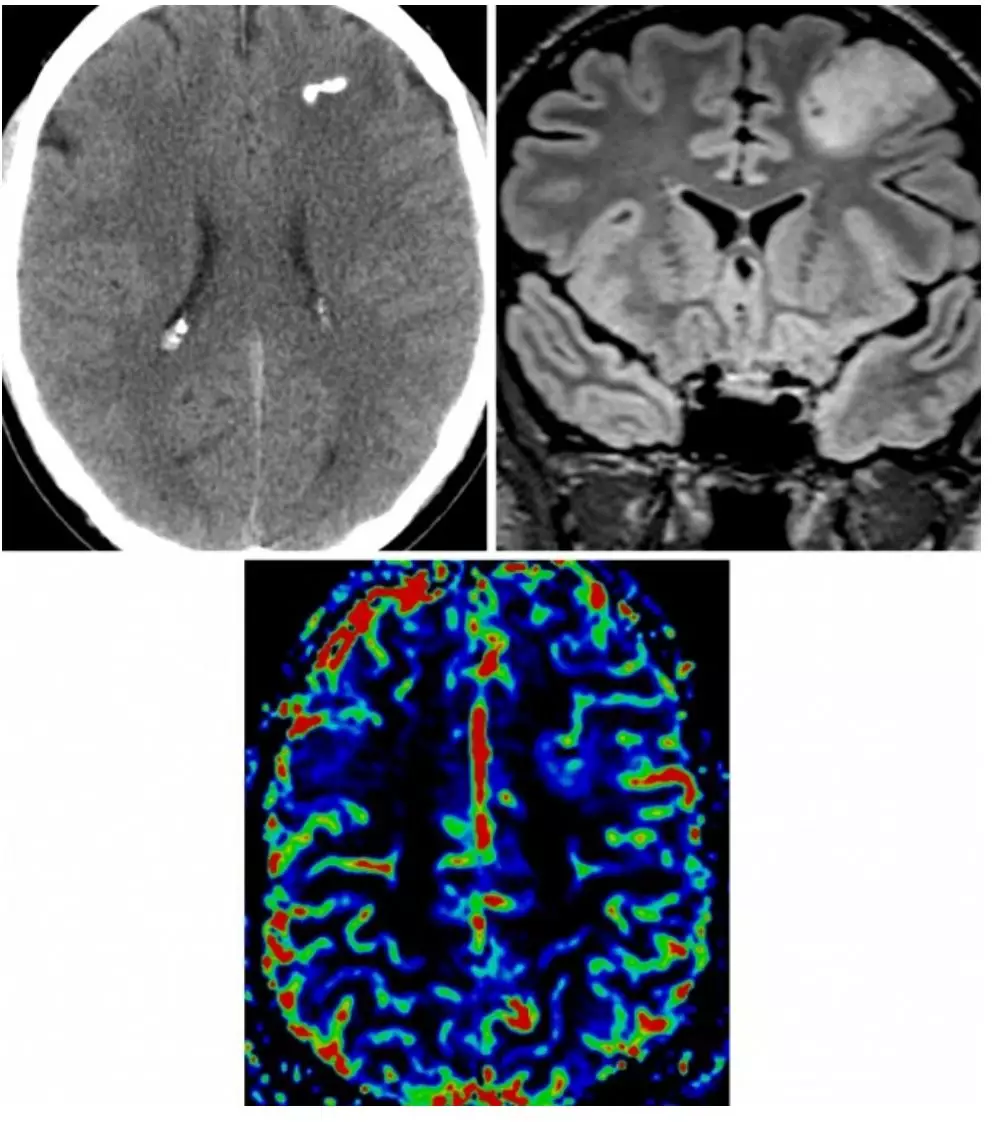

图1. 少突胶质细胞瘤在CT上的特征性改变为肿瘤内部的多发钙化(左上图);在冠状位FLAIR上,肿瘤典型的表现为均匀局限性浸润生长,累积周围的皮层及白质(右上图);在脑血容量灌注图像上,少突胶质细胞瘤表现为轻微低灌注,出现“鸡笼”样血管的病理特征(下图)。

CT

(1)发生于幕上的累及皮质及皮质下白质的等低密度团块影

(2)如果有出血或钙化则表现为局灶性高密度影

(3)CT增强表现为多变的强化效应

(6)MR波谱成像/MR灌注成像:胆碱升高,NAA下降,脂质及乳酸峰缺失(不同于间变性少突胶质细胞瘤);具有相对脑血容量(RCBV)升高的独特特征,但是由于出现“鸡笼”样血管的病理特征,RCBV分级较低